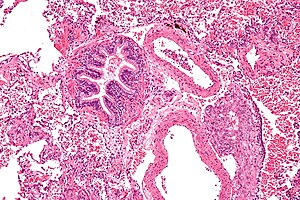

Lymphangioleiomyomatosis. H&E stain. | |

Microscopic

Features:[6]

- Spindle cells with small nuclei + larger epithelioid cells with clear cytoplasm and round nuclei.

- Cyst formation.

- Thick arterial walls.